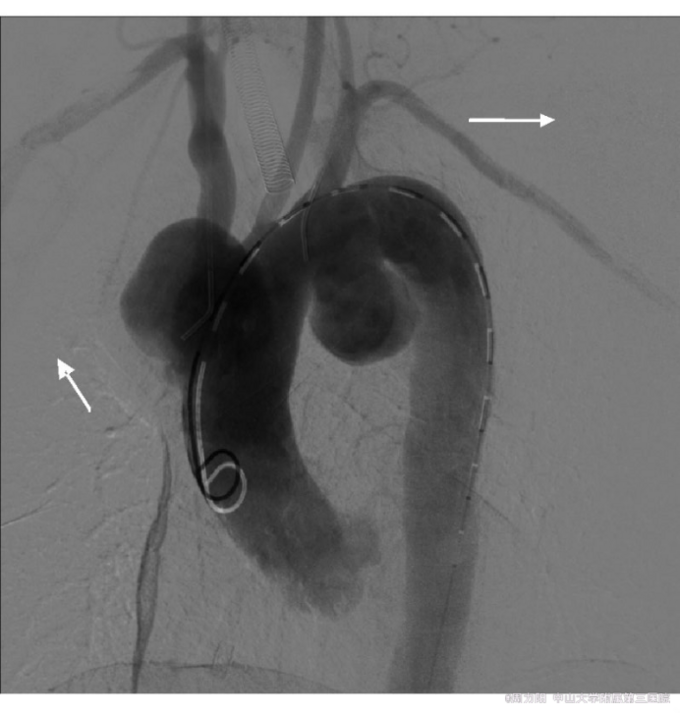

根据患者进行性声音嘶哑,心脏杂音,主动脉造影的动脉瘤的部位、形态均符合梅毒性主动脉瘤的特点,梅毒血清学试验阳性,故诊 断为“梅毒性主动脉瘤”. 治疗:患者青霉素皮试阳性,故予头孢曲松第1天0.2g,第2天0.4g,第3天0.8g,第4天起2g/d,共2周,治疗前1天开始予泼尼松10mg2/d,口服,共3d,并控制血压、血脂,抗血小板聚集。后于血管外科行血管支架植入术。